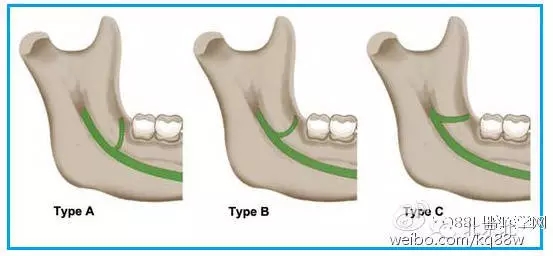

圖一 磨牙后區(qū)的形態(tài)學(xué)分類(綠色標(biāo)示):A.水滴形;B.細(xì)長型;C.三角形。